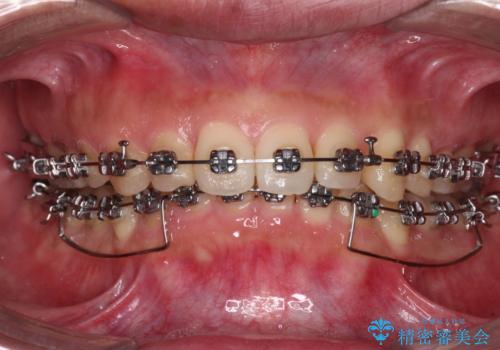

- 矯正装置

- メタルブラケット

下顎前歯が見えなくなるくらいに深い咬み合わせであり、さらに上顎の正中が開くほど下の前歯が突き上げている状態でした。

奥歯は手前に倒れてしまっているため、後方に起き上がらせることで深い咬み合わせ・ディープバイトを改善する必要があります。

ディープバイトの方は項合力が強大であることが特徴のため、仕上がりを重要視して、ワイヤー装置にて矯正治療を行うこととしました。